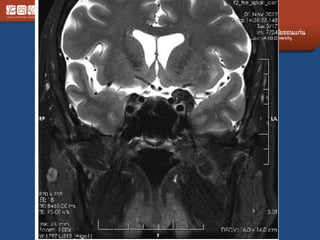

Meningioma

• Different shape from adenoma

• Diaphargma sellar = depressed

• #Craniopharyngioma

– Ddx dermoid (less likely)

• Bimodal distribution 5-15, 40-60

• 2 types

– Adamantinomatous : child with cal

– papillary

• Benign but adhere tightly

• Suprasellar, intrasellar, 3rd vent, sphenoid sinus,

nasopharynx

• Cystic solid, calcified mixed